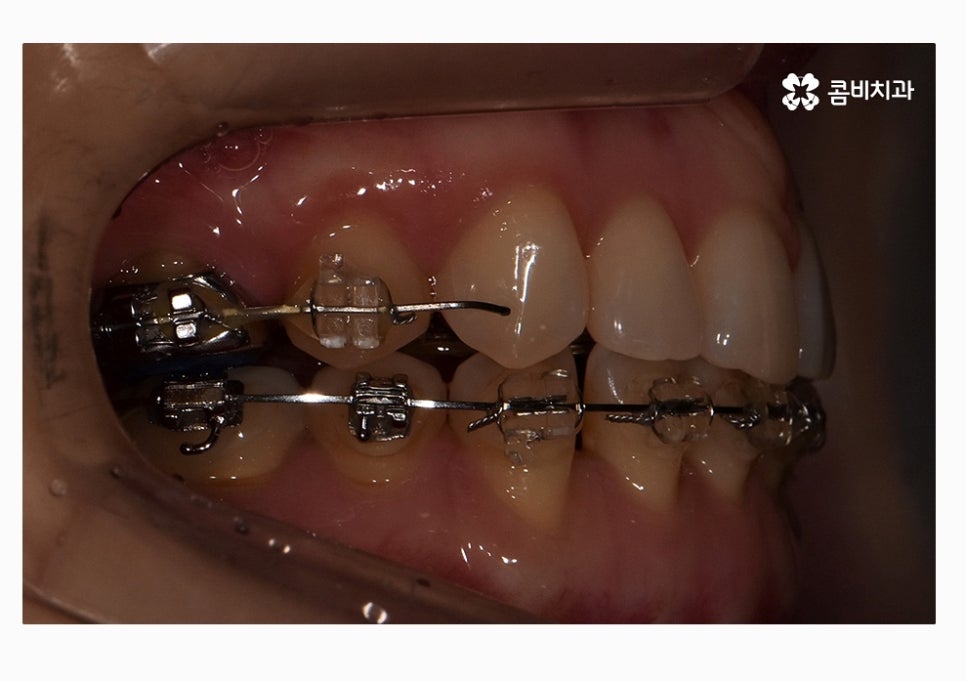

치열 사진을 볼 때 정면보다는 옆모습으로 볼 때

아래 어금니가 위 어금니보다 앞으로 나와있고

앞니 교합이 제대로 맞물리지 않는다는 것이 눈에 띄게 나타나는데

콤비교정은 윗니는 치아의 안쪽에 교정기를 부착하고

아랫니는 치아의 바깥쪽에 장치를 부착하는 방법으로

위 환자분의 경우에는 콤비교정의 치료 경과를 보면

아랫니가 정상교합이 되었고 치열도 보다 가지런하게

변화되고 있음을 알 수 있는데요.